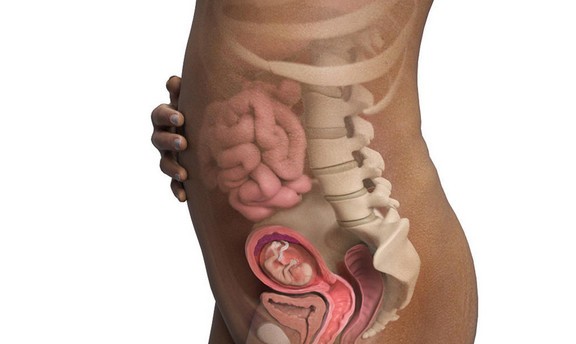

الأسبوع السابع والعشرون

خلال هذا الأسبوع يبدأ شكل الجنين بالوضوح ويصبح قريباً للشكل الذي يظهر به الجنين عند الولادة، ولكن مع اختلاف أنه صغير الحجم كما أ هناك بعض الأعضاء لم يكتمل نموها بعد مثل الرئتين والكبد، جدير بالذكر أن هناك حالات معينة يولد فيها الطفل خلال هذا الأسبوع ويعيش بشكل طبيعي جداً إذا تم الاهتمام والعناية به من قبل الأطباء بعد ولادته.

الأسبوع الثامن والعشرون

تبدأ جفون الطفل بالتفتح وتتشكل رموشه خلال هذا الأسبوع كما يبلغ وزنه 1 كيلو وكذلك يمكن ولادته بهذا الأسبوع وتصبح فرص حياته كبيرة بنسبة تتعدى ال90%.

الأسبوع التاسع والعشرون

تكتمل العظام لدى الجنين خلال هذا الأسبوع لكنها ما زالت هشة وغير صلبة.

الأسبوع الثلاثون

خلال الأسبوع الثلاثون يكتمل نمو شعر الجنين وتزداد لديه القدرة على فتح عينيه بشكل أكبر ويتم إنتاج خلايا الدم الحمراء في النخاع العظمي ويصبح وزن الجنين بنهاية هذا الأسبوع كيلو و300 جرام.

الأسبوع الواحد والثلاثون

يصبح جسم الجنين بهذا الأسبوع قادر على التحكم بحرارة جسمه وذلك بفضل نمو وتطور جهازه العصبي ويستمر الجنين بالنمو حتى نهاية الأسبوع.

الأسبوع الثاني والثلاثون

يبدأ الجنين خلال هذا الأسبوع بالتمرن على كيفية التنفس وذلك ولم تكتمل الرئة لديه بعد، ويبدأ الشعر الوبري الموجود على جسم الجنين بالتساقط وتنمو الأظافر ويستطيع الجنين امتصاص العديد من المعادن من أمعاء الأم.

الأسبوع السابع والثلاثون

خلال هذا الأسبوع يبدأ موعد الولادة بالاقتراب ويبدأ رأس الجنين بالنزلاق تجاه منطقة الحوض وبالطبع يجب المتابعة مع الطبيب المختص خلال هذه الفترة لمعرفة آخر التطورات.

الأسبوع الثامن والثلاثون

يتكمل نمو الطفل خلال هذا الأسبوع ويصبح على استعداد لأن يتم ولادته ويصبح وزن رأسه حوالي 400 جم أما عن وزن الجسم بشكل عام فيبلغ 2900جم .

الأسبوع الأربعون

هذا الأسبوع هو الأسبوع الذي يفترض أن تتم فيه الولادة ويكون حجم الجنين خلاله 50 سم ووزنه حوالي 2900 جم ويختلف الأحجام بفروقات بسيطة من جنين لآخر ولكن المشترك في الموضوع أن أجهزة الجسم اكتملت وأصبحت تعمل بصورة سليمة لا تؤثر على حياة الطفل بعد ولادته.